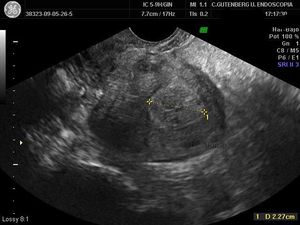

Abnormal uterine peristalsis is a likely a cause of infertility, and can result from the presence of intramural fibroids